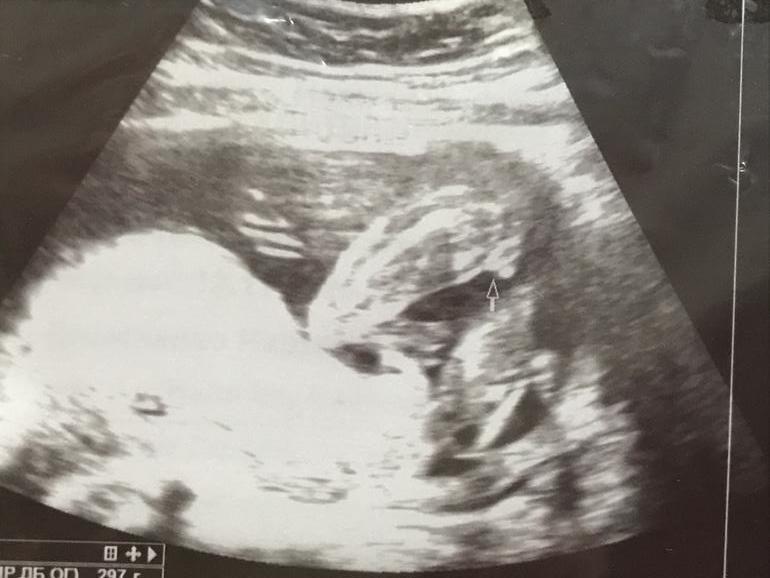

Вопросы про УЗИ, обследования и анализы: что, где, как, когда?Кто-нибудь разбирается как определить? Посмотрите пожалуйста)

На скрининге сказали девочка. Потом вот пошла в платную чтобы убедиться, сказали 70% девочка дали это фото

А при чем тут наклоны? Тут уже 20 недель человеку, все сформировано 👍🏻